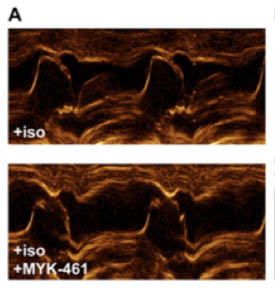

image with two panels comparing obstructed and clear pathways for blood flow

One image of many in Dr. Stern’s published article that shows clearer pathways for blood flow after MYK-461 treatment (bottom panel) in cats with hypertrophic cardiomyopathy.

Specifically, in the study, treatment with MYK-461 eliminated obstruction in the left ventricle in five cats with HCM. This means that the novel drug may help keep excessive growth of the heart’s walls at bay — without surgery or interventional procedures — so the heart can pump and blood can flow easily and efficiently. The hope is that because of improved heart function, cats with HCM may enjoy a longer lifespan and high quality of life during that time.